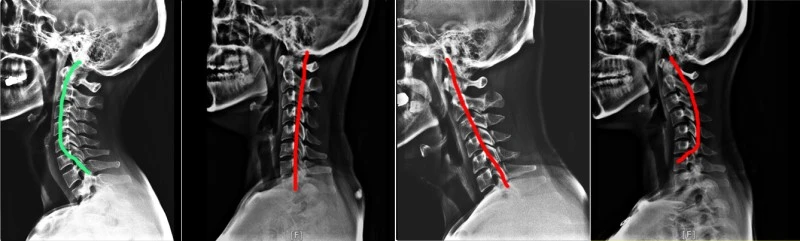

왼쪽부터 정상 C자형 목 / 일자목 / 거북목 / 역C자형 목

C자형 목이 외부에서 오는 충격을 흡수해야 하는데 역 C자형 목은 충격을 흡수하지 못해서 머리 무게(6kg 정도인데 충격 흡수를 못하면 27kg의 힘이 전해진 다고 한다...)와 외부 압력이 그대로 근육에 가해지게 되고 그 스트레스가 근육에 계속 쌓이면 신경을 건드려서 지금처럼 뒷목과 등, 팔까지 전해져 오는 요상한 통증을 느낄 수 있다고 한다.